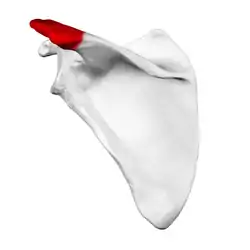

Extrinsic factors

Well-documented anatomic factors include the morphologic characteristics of the acromion, a bony projection from the scapula that curves over the shoulder joint. Hooked, curved, and laterally sloping acromia are strongly associated with cuff tears and may cause damage through direct traction on the tendon.[19] Conversely, flat acromia may have an insignificant involvement in cuff disease and consequently may be best treated conservatively. The development of these different acromial shapes is likely both genetic and acquired. In the latter case, there can be a progression from flat to curved or hooked with increasing age.[19] Repetitive mechanical activities such as sports and exercise may contribute to flattening and hooking of the acromion. Cricket bowling, swimming, tennis, baseball, and kayaking are often implicated. Progression to a hooked acromion could be an adaptation to an already damaged, poorly balanced rotator cuff with resultant stress on the coracoacromial arch.[19] Other anatomical factors include an os acromiale and acromial spurs. Environmental factors include age, shoulder overuse, smoking, and medical conditions that affect circulation or impair the inflammatory and healing response, such as diabetes mellitus.[19]